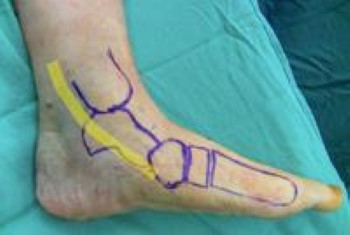

Location of posterior tibial tendon

The most common location of pain is along the course of the posterior tibial tendon (yellow line), which travels along the back and inside of the foot and ankle.